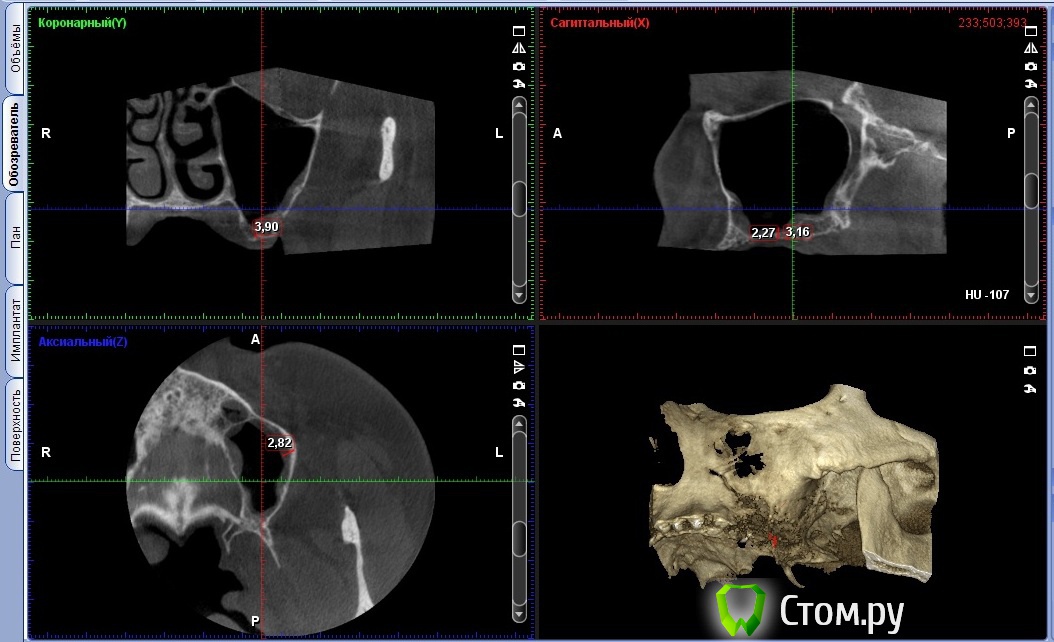

Andex Опубликовано 15 января, 2014 Поделиться Опубликовано 15 января, 2014 Один из первых синусов по открытой методике. Во время работы перфорировал шнайдерову, наложил на место перфорации "special", графт от альфа-био, на окно эволюшн. Прошло 6 месяцев, жалоб как не было с операции, так и нет сейчас. Фото до операции фото после(на сегодня такой вид)Какие ошибки были допущены? Что делать дальше?Мой план - закрытый синус с одномоментной установкой 3х винтов, помолиться, подождать 6 мес и протезировать. Только я считаю-что осложненений нет только у того,кто не работает?Благодарю за обоснованную критику и разумные советы)))) Ссылка на комментарий

vesvova Опубликовано 27 января, 2014 Поделиться Опубликовано 27 января, 2014 Кому было интерестно - фото после операции. Сделал сразу все фотки - до и после. Интересует обоснованная критикаНу эти фотки мало о чем говорят.ТОлько КТ может дать оценку. Вы лучше расскажите, как удалось отслоить мембрану? Что в пазухе- окостеневший графт или "каша" из графта с фиброзом? 2 Ссылка на комментарий

Andex Опубликовано 29 января, 2014 Автор Поделиться Опубликовано 29 января, 2014 тоже интересно Если четно - не знаю на 100% что там. Тк принял решение делать зыкрытый синус. Почитал мнения более опытных и мною уважаемых коллег с форума в этой ветке-что надо делать открытый и ревизию. Когда отслоился - в месте окна после первого синуса очень плотная и толстая кость(по сравнению с с костью до операции), плюс из-за того,что было жалко выбрасывать мембрану-я перекрыл ей не только окно,а еще и крестальную кость, что в итоге дало +1 мм по высоте. На КТ этого видно не было почему то. Все взвесив, сделал закрытый. По ощущениям - графт закладывался намного труднее(туже) чем при классическом закрытом синусе. Всего ушло 1,5 мл на 3 лунки. Импланты 25з - 3.75х10, 26з - 4.2х10, 27з - 4.2х10, торк на всех 40 н/см. Подозреваю,что в пазухе все же фиброзно-графтовая каша. Время покажет праивльно я поступил или нет, или же надо было прислушаться к советам. Но это мое решение, и отвечать за него тоже буду я) 1 Ссылка на комментарий